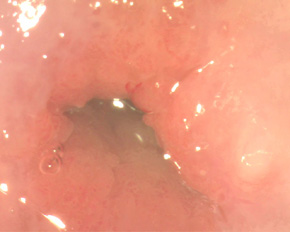

Лікування ерозії шийки матки методом аргоноплазменной абляція (коагуляція). Прогресивно новим методом лікування ерозії шийки матки є аргоноплазменной абляція (коагуляція) шийки матки. Метод аргоноплазменной абляції (коагуляції) - це вплив на тканини плазмою, що формується іонізованим аргоном. Це безконтактна процедура, без дотику інструменту до тканин. Безпечне вплив на тканини внаслідок чітко контрольованої глибини проникнення. Без обвуглювання і димленія тканин, відсутність неприємних запахів при маніпуляції. Ефективно застосовується для поверхневої коагуляції, однорідного гемостазу і девіталізациі тканин. Щадне лікування патології шийки матки - дисплазія шийки матки , Ерозія шийки матки - відбувається практично безболісно, не залишає рубців і широко використовується для лікування ерозії шийки матки і дисплазії шийки матки у родили жінок. Процедура є цілком безпечною, тому що глибина проникнення факела аргоновой плазми становить 0,5 мм до 3 мм.Естественно, аргоноплазменной абляция широко застосовується і у жінок, які народили, завдяки своїй надійності, ефективності і безопасності.Современний апарат для лікування патології шийки матки «Фотек 401» поєднує в собі можливість застосування радіохвильової коагуляції (для лікування більш глибоких поразок, особливо при вираженій деформації шийки після пологів в поєднанні з ерозією шийки матки) і аргоноплазменной абляції - при ерозії шийки матки. Подібних установок в Україні не багато, це обумовлено їх порівняно високою вартістю. При проведенні коагуляції аргоном, хворобливість незначна або практично повністю відсутня. Після процедури необхідно дотримуватися статевої спокій 1 міс. Виділення після пріжіганіяерозіі шийки матки з статевих шляхів можуть незначно посилитися, але це не буде доставляти дискомфорт у повсякденному житті. Повне загоєння проходить за 2 місяці. Вагітність планувати можливо вже через 3-6 міс після процедури.